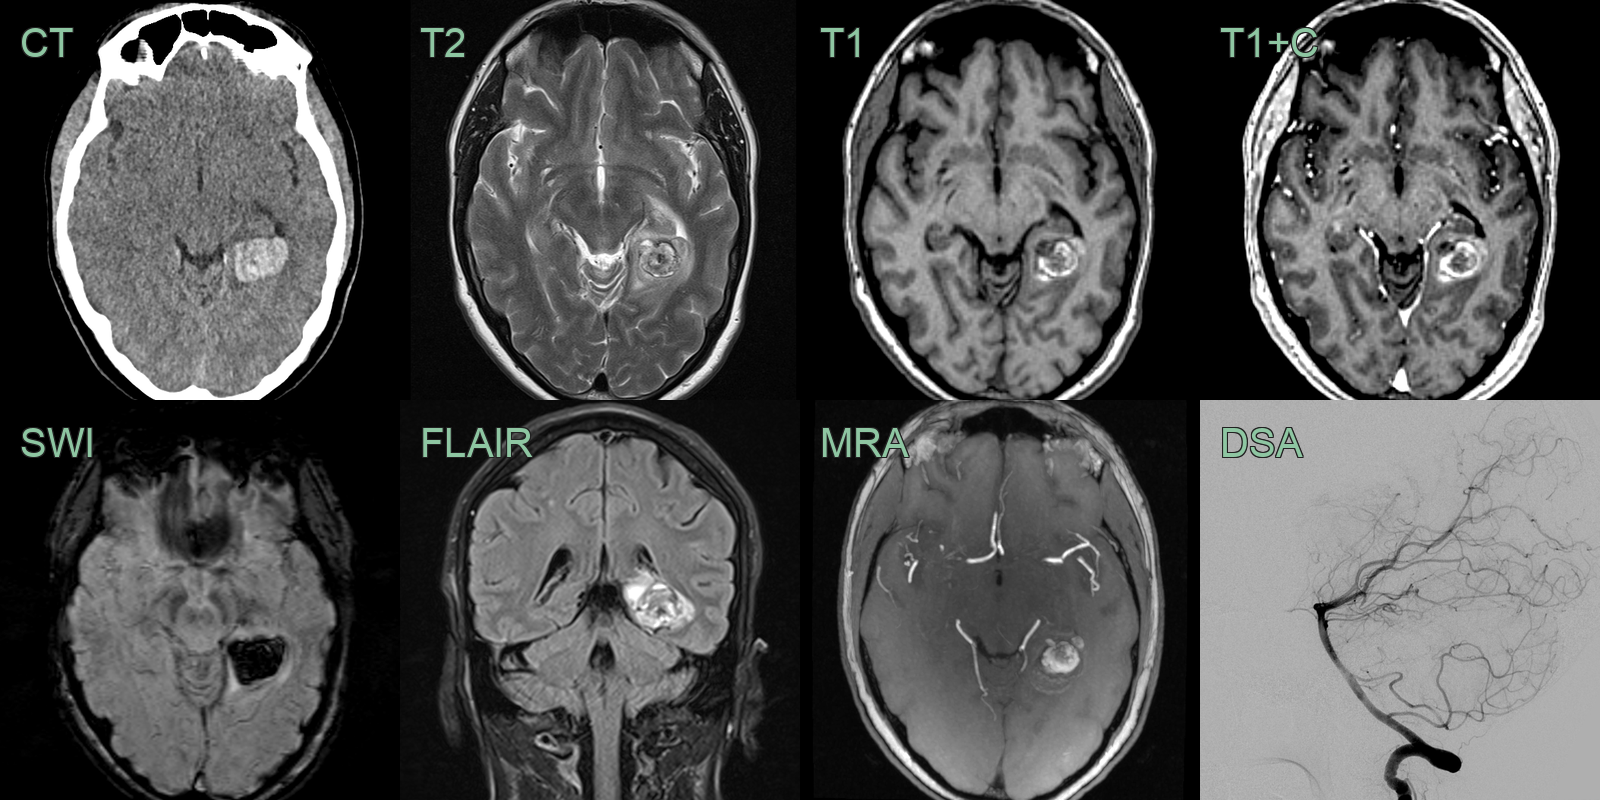

CT

- Potentially hyperdense due to calcification or acute hemorrhage

MRI

- T2 "Popcorn" or "mulberry" appearance with mixed signal intensity

- SWI Hypointense due to hemosiderin deposition and potentially calcification

- T1 Variable depending on presence or age of blood product

- ++T1+C++ Absent (or minimal) enhancement

Catheter angiogram

- Not visible on DSA ("angiographically occult")